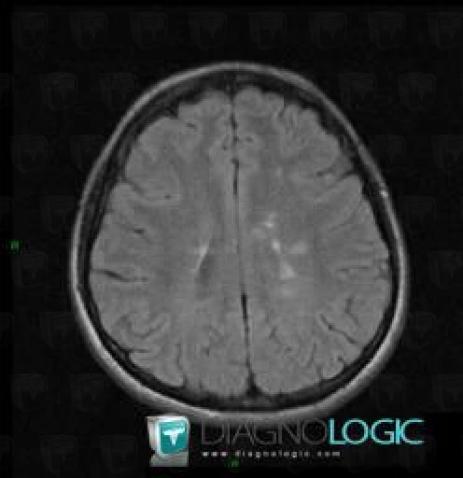

Multiple sclerosis, Cerebral hemispheres, MRI

Here is the specific information in the key image above:

- Diagnosis Multiple sclerosis, Location(s) Cerebral hemispheres, with gamuts Intracerebral T2W or FLAIR hyperintense lesion, White matter disease, Multifocal intracranial lesions